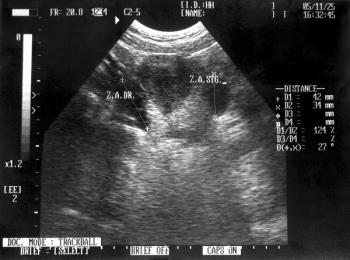

Investigators found significant shifts in diagnosis of and prescriptions for pulmonary hypertension (PH) when exercise right heart catheterization was used.